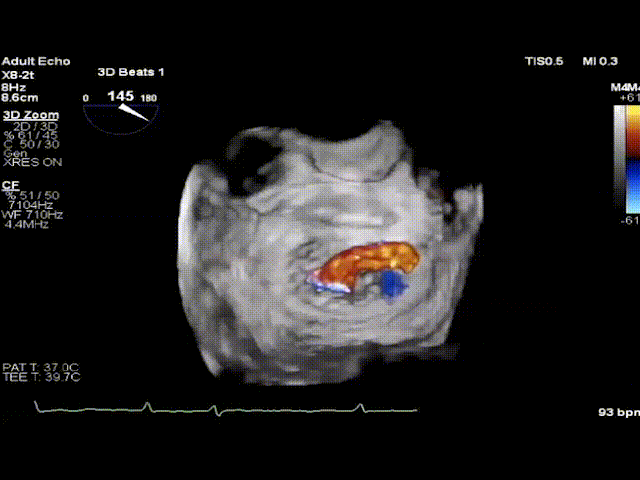

2021年12月22日,四川大学华西医院心脏内科陈茂、冯沅教授联合心脏外科蒙炜教授、麻醉科朱涛、陈果教授等组成的多学科团队完成了HighLife TSMVR技术的亚洲首例临床应用。手术过程顺利,人工瓣膜植入位置理想,术后即刻二尖瓣返流完全消失,无左室流出道梗阻,患者恢复良好。该例手术亦是亚洲地区开展的首例经房间隔二尖瓣置换术!

术后即刻超声评估